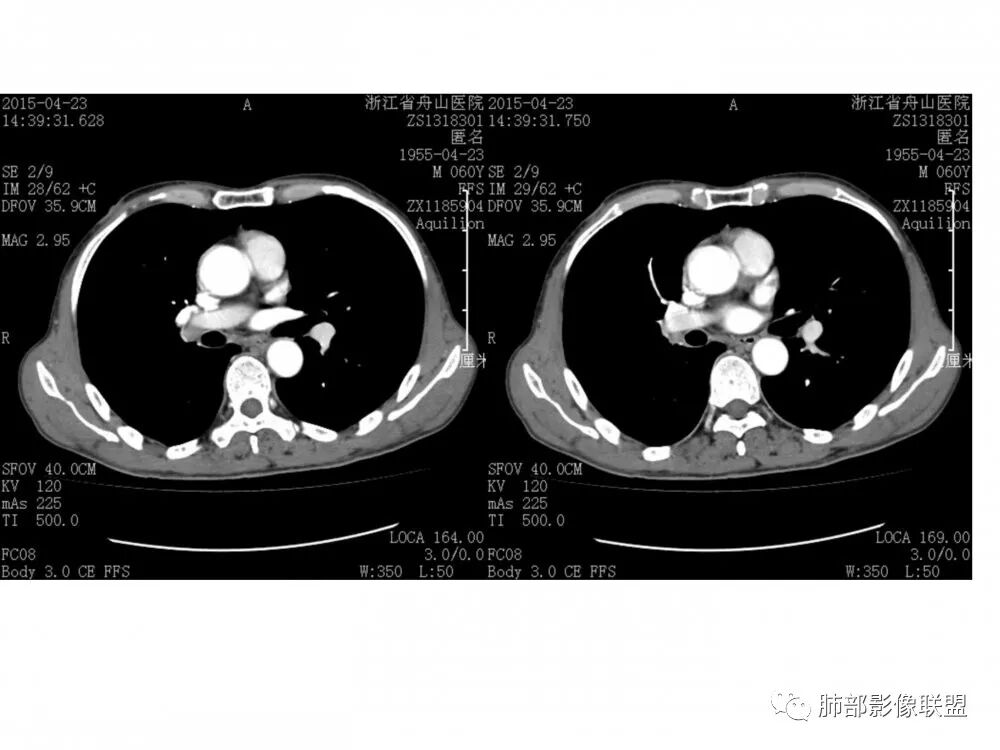

右肺下叶支气管腔内肿块,沿着支气管生长,支气管壁破坏,中度强化,纵膈及肺门淋巴结肿大,老年男性,首先考虑小细胞肺癌,其次腺样囊腺癌。类癌女性多见,明显强化,淋巴结肿大少见。鳞癌常有远端阻塞炎症及肺不张,淋巴结肿大少见。

男,60岁,右侧肺门肿块影,右肺下叶支气管壁增厚,管腔狭窄,截断,增强扫描,病灶明显强化,密度不均,纵隔内见多发肿大淋巴结,考虑腺癌可能,鉴别鳞癌,小细胞癌。

右肺下叶支气管开口新生物,轴位管腔及纵向基底干大部分受累狭窄,支气管管壁破坏并突破形成腔外肿块,血管累及变细,肉眼观轻度强化,右肺门、纵膈淋巴结肿大,恶性没问题,阻塞性炎症不明显,类癌强化明显不支持,老年男性,首先考虑小细胞癌,鉴别不典型鳞癌和腺癌。

老年男性,右肺下叶支气管内软组织影,感觉沿支气管黏膜下生长,管腔狭窄,增强呈轻度强化,右肺门及纵隔多发淋巴结增大,考虑恶性,神经内分泌癌,娘小崽大,考虑小细胞肺癌,鉴别粘液表皮样癌,类癌